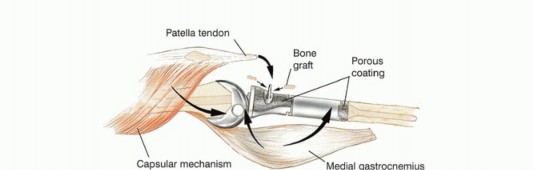

آلية المد

يتم استئصال موقع ارتباط آلية المد (الوتر الرضفي عند حديبة قصبة الساق) بشكل كتلة واحدة مع قصبة الساق القريبة. إعادة بناء هذه الآلية أمر ضروري لوظيفة الطرف المصاب. بدون إعادة بناء فعالة، قد يعاني المريض من ضعف كبير في القدرة على مد الركبة، مما يؤثر على المشي والحركة.

الاستئصال الجراحي وإعادة البناء

هناك عدة خيارات لإعادة بناء العيب الهيكلي بعد استئصال الورم:

- الاستبدال بالطرف الصناعي (Prosthetic Replacement): هذا هو الخيار المفضل في عيادة الأستاذ الدكتور محمد هطيف. توفر الأطراف الصناعية نتائج وظيفية أفضل بكثير وتقلل من مخاطر عدم الالتئام والعدوى مقارنة بالطعوم العظمية.

دور سديلة العضلة التوأمية الإنسية (Gastrocnemius Rotational Flap)

يُعد استخدام سديلة العضلة التوأمية الإنسية (عضلة الساق) عاملاً رئيسياً في تحقيق تغطية كافية للأنسجة الرخوة للطرف الصناعي واستعادة وظيفة آلية المد. تُنقل هذه العضلة لتدور إلى الأمام لتغطية الطرف الصناعي، مما يقلل بشكل كبير من خطر العدوى ومضاعفات الجروح، وهو ما كان يمثل تحدياً كبيراً في الماضي. يؤكد الأستاذ الدكتور محمد هطيف على أن هذه التقنية أصبحت إجراءً روتينياً وموثوقاً لضمان تغطية الطرف الصناعي وتقليل معدل العدوى ونخر السديلة والبتر الثانوي.

تفاصيل الإجراء الجراحي للحفاظ على الطرف

تُعد جراحة الحفاظ على الطرف في أورام قصبة الساق القريبة إجراءً معقداً يتطلب خبرة جراحية عالية وتخطيطاً دقيقاً. يقوم الأستاذ الدكتور محمد هطيف بتطبيق أحدث التقنيات لضمان استئصال الورم بشكل كامل وإعادة بناء الطرف بأمان وفعالية. تتضمن الجراحة ثلاث خطوات رئيسية:

- استئصال الورم: إزالة الجزء المصاب من قصبة الساق والأنسجة المحيطة به مع هامش أمان كافٍ.

- إعادة بناء العيب الهيكلي ومفصل الركبة: زرع طرف صناعي أو طعم عظمي لاستبدال الجزء المستأصل.

- إعادة بناء آلية المد وتغطية الطرف الصناعي بالأنسجة الرخوة: استخدام سديلة العضلة التوأمية لضمان التغطية والحفاظ على وظيفة الركبة.